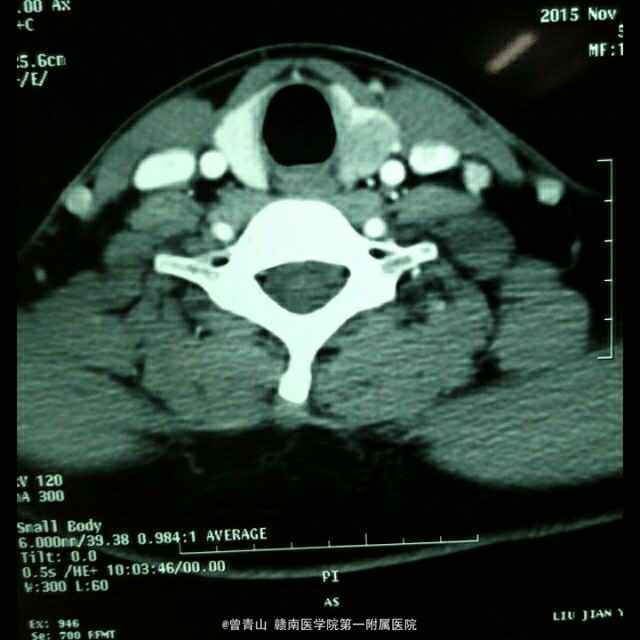

患者男性,20岁,因“咽部不适20天,发现颈部包块1天入院” 患者因咽部不适,吞咽异物感就诊于当地医院,一直给予针对慢性咽喉炎治疗,无明显效果。患者于昨日就诊于我科门诊,查体发现左侧甲状腺肿大,给予彩超检查发现左侧甲状腺肿物。

查体:心肺腹未见异常,口腔面膜充血,咽部见淋巴滤泡。甲状腺触诊发现左侧Ⅱ度肿大,边界不清,活动度尚可。 CT,彩超

诊断:甲状腺癌、慢性咽喉炎 治疗:手术方式~甲状腺左侧腺叶+峡部切除+喉返神经解剖术+中央区淋巴结清扫